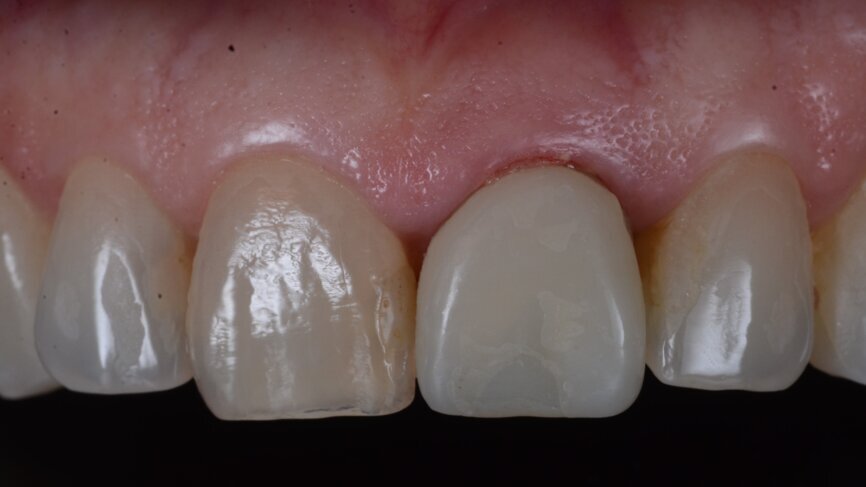

A 53-year-old female patient presented to the office with a fractured left central incisor which had been repeatedly bonded to a ceramic crown (Figs. 1 & 2). Anamneses and examination established good systemic and oral health, a well-balanced occlusion and no smoking habits. Cone beam computed tomography (CBCT) and a periapical radiograph showed external root resorption with very limited insertion into the alveolar bone, insufficient for adequate conventional intra-radicular post placement (Figs. 3 & 4). Considering that the fractured tooth was in the aesthetic zone, the patient requested restoration in the safest and fastest way possible.

Fig. 1: Initial situation, extra-oral view.

Fig. 2: Initial situation, intra-oral view.